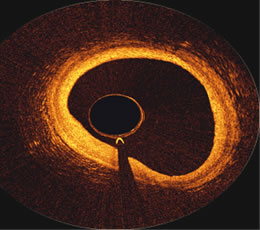

OCT

image inside the proximal portion of a Right Coronary Artery,

courtesy of

the First in Man Volcano OCT,

performed at ThoraxCenter

in

Rotterdam

by Prof. Patrick Serruys

and Dr. Evelyn Regar |